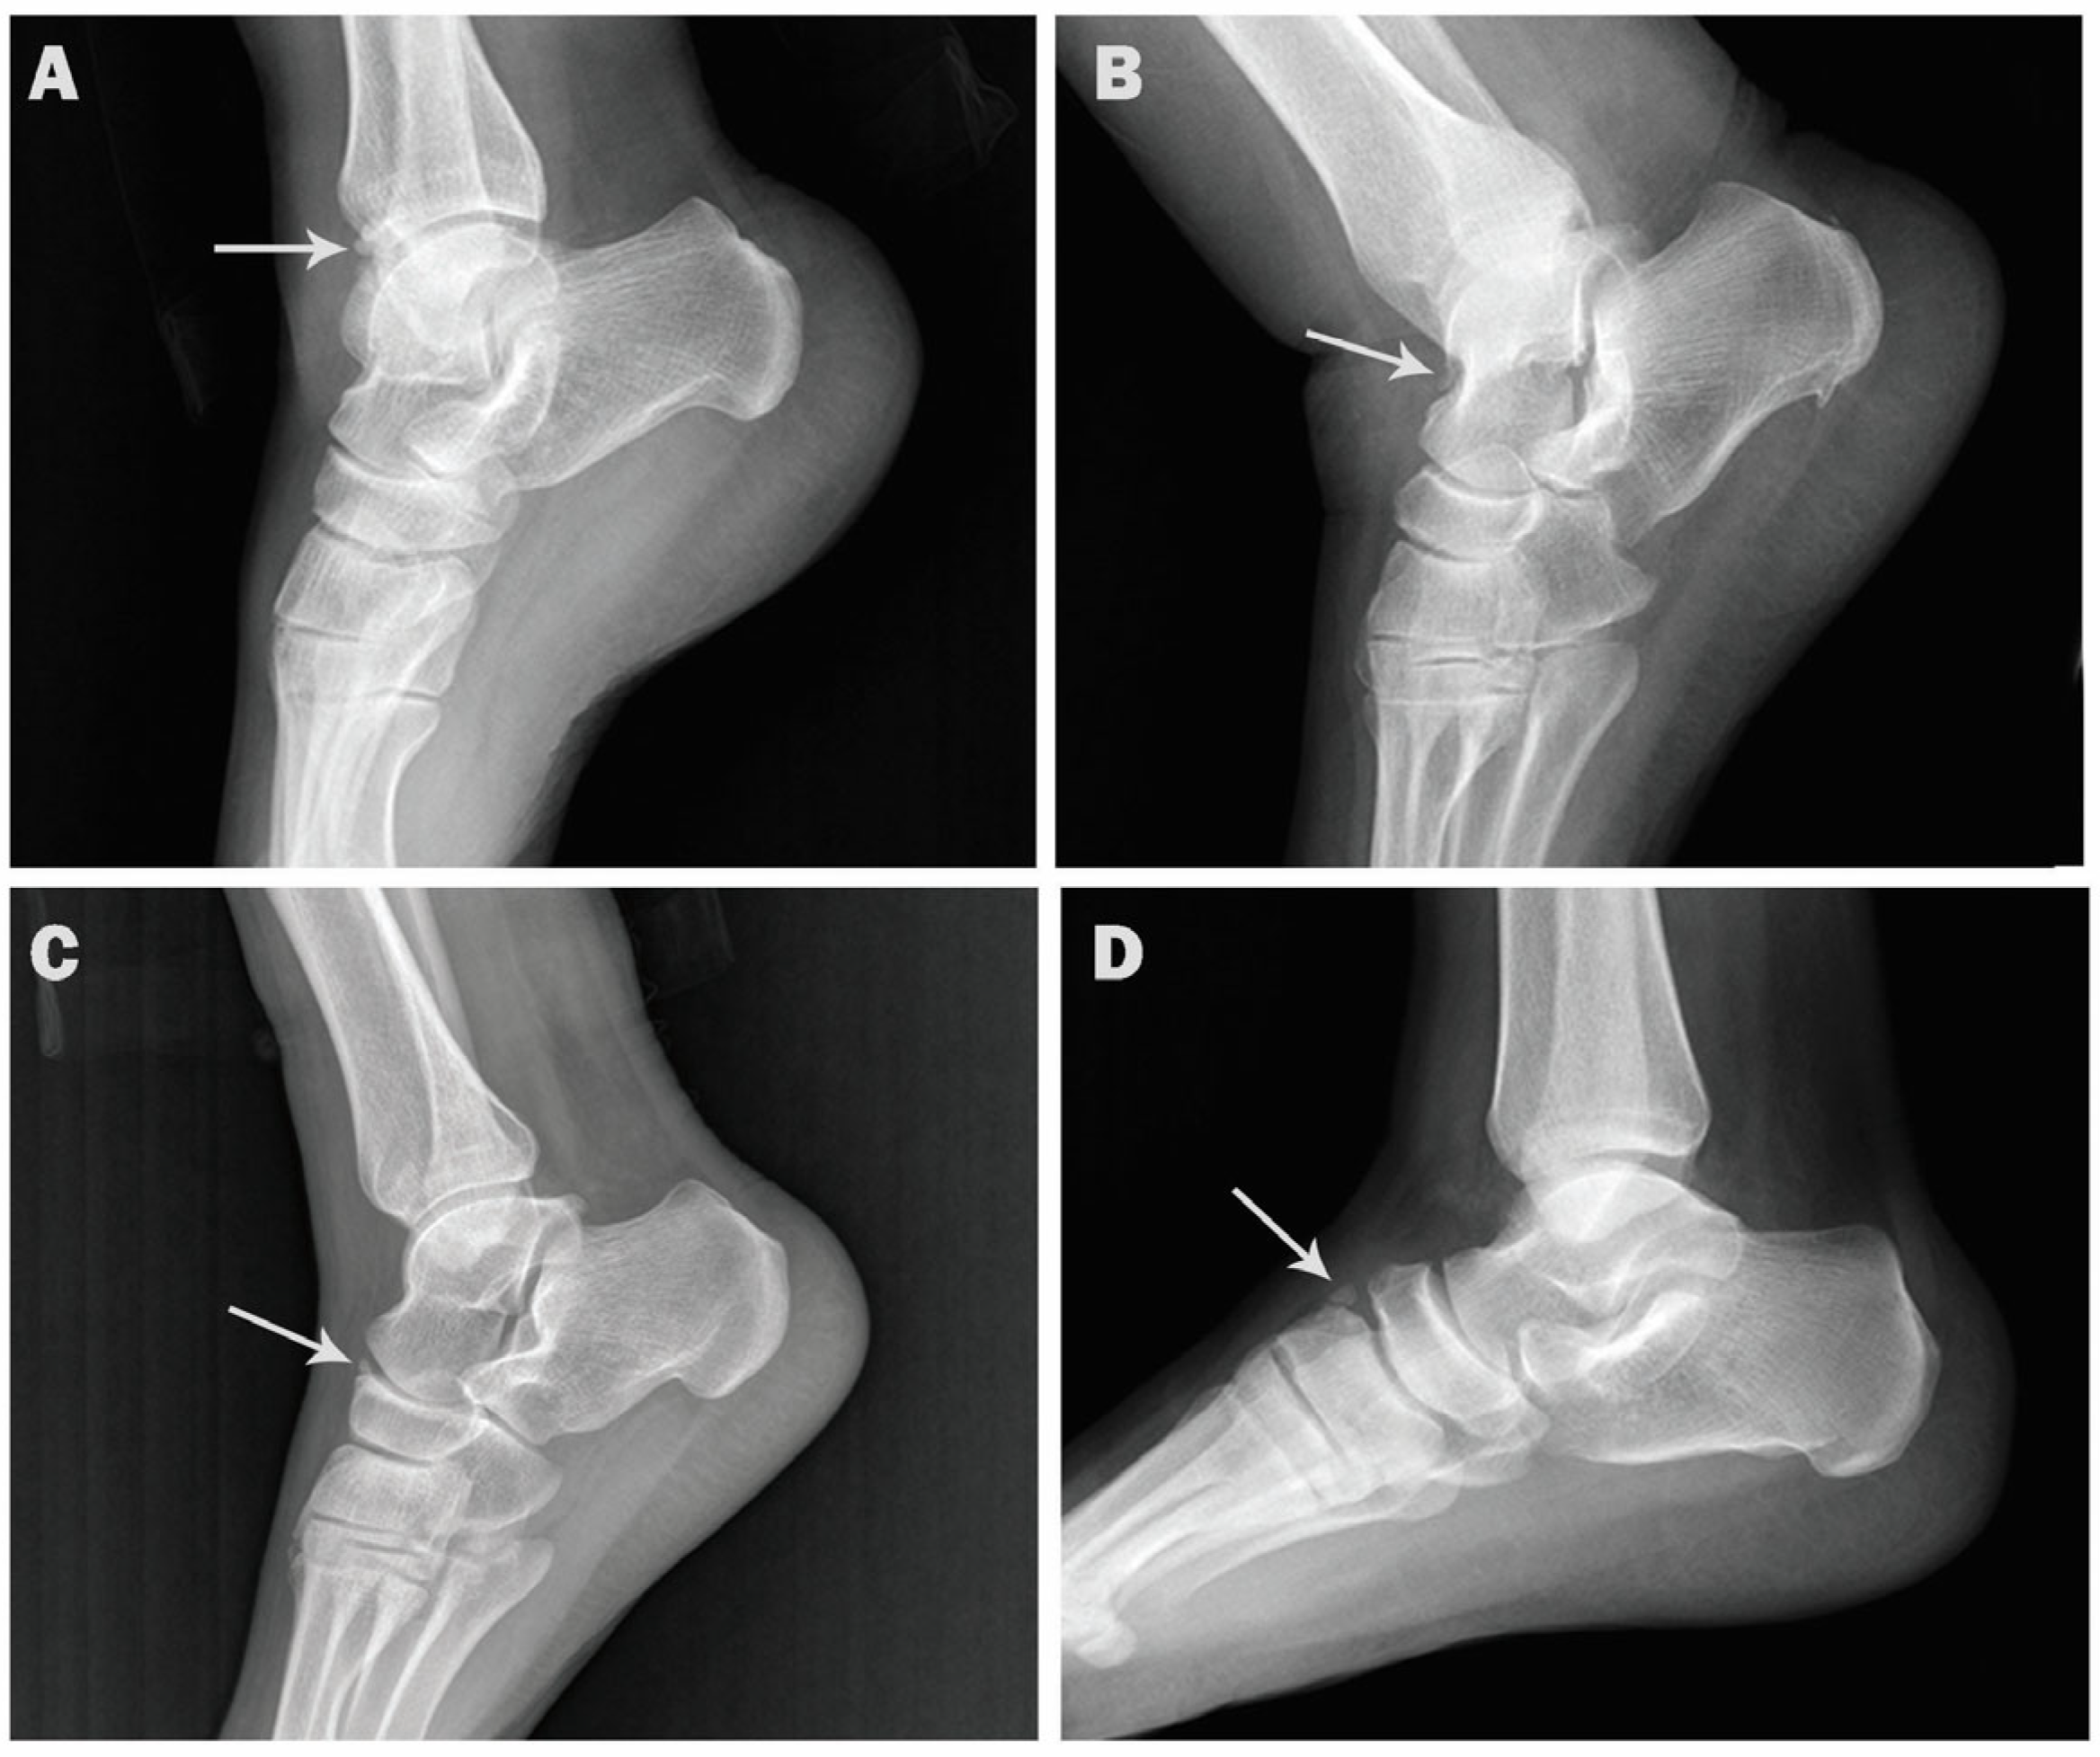

Figure 1 from The Accessory Ossicles of the Foot and Ankle ; a What Is A Accessory Ossicle They are often noted incidentally during evaluation of foot and ankle. It usually forms in the inner part of the foot, right above the arch. Accessory ossicles are a common radiographic finding about the foot and ankle in children and adolescents. Accessory ossicles are secondary ossification centers that remain separate from the adjacent bone. They are usually round or ovoid. What Is A Accessory Ossicle.

Figure 4 from Rare and common ossicles of the lower extremity Imaging What Is A Accessory Ossicle Accessory bones also go by the name accessory ossicle simply because they tend to be small round bones. The accessory navicular bone is a surplus piece of cartilage or bone fragment. What is an accessory navicular? They are often noted incidentally during evaluation of foot and ankle. They are usually round or ovoid in shape, occur in typical locations and.. What Is A Accessory Ossicle.